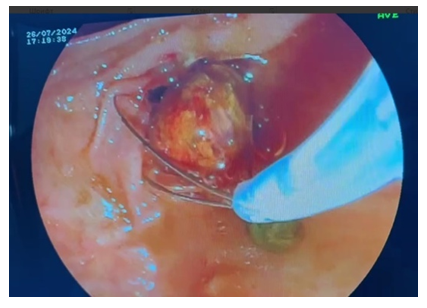

As can be seen from the table above, laparoscopic cholecystectomy was performed in 34 (56.6%) cases in patients with ACP; Laparoscopic cholecystectomy with assisted EPST using the Rendezvouz technique (LERV) – in 11 (20%) cases, and EPST and Laparoscopic cholecystectomy – in 7 (12.7%) cases with ACP combined with choledocholithiasis. In 10 (16%) cases of ACP in patients with concomitant somatic diseases and in elderly and senile patients, puncture interventions with drainage of the gallbladder under visual ultrasound control were performed at the first stage, followed by laparoscopic cholecystectomy at the second stage after improvement of the general condition of patients and indicators of endotoxemia, as well as adequate preoperative preparation, Of these, 4 have EPST supplemented at the 2nd stage.When performing LERV in patients of the first group (11 patients), the gallbladder was removed laparoscopically and the common bile duct was sanitized by endoscopic access through the Large duodenal papilla (LDP). At the first stage, after the cystic artery was isolated, it was clipped with a 5 mm titanium clip and crossed using an U-shaped hook using monopolar cutting. Next, the cystic duct was isolated at its maximum extent. After applying a 5 mm titanium clip to the cystic duct in its distal part, closer to the neck of the gallbladder, an incision of the cystic duct was performed below the applied clip to perform intraoperative direct cholangiography (Fig. 1, 2).  | Figure 1. Intraoperative cholangiography using forceps |

During the second stage of surgery (Rendezvous), joint work of surgical and endoscopic teams is necessary. The surgeon performed an incision of the cystic duct just below the previously applied clip and inserted a 0.035 Fr endoscopic string 450 cm long into the cystic duct through a 3 mm diameter trocar. Then he conducted it antegradely through the LDP into the lumen of the duodenum. After the string was passed through the LDP, the endoscopist conducted a video duodenoscope in the duodenum in the usual way and visualized the LDP in the lumen of which the string was located. From the side of the lumen of the duodenum, the string was captured with a modified hollow endoscopic bougie (Fig. 3).At the third endoscopic stage of the hybrid surgical intervention, the papillot was lowered along the string and inserted into an ampoule of LDP, thus performing selective intubation of the choledochus. Retrograde endoscopic papillosphincterotomy (EPST) was performed using the standard method (Fig. 4).Then the papilloma was removed, leaving an endoscopic string in the biliary tract. Depending on the diameter of the common bile duct and the size of the stones, lithoextraction was performed with four-string Dormia baskets of various sizes and stiffness (Fig. 5).  | Figure 3. Capturing the string in the lumen of the duodenum |